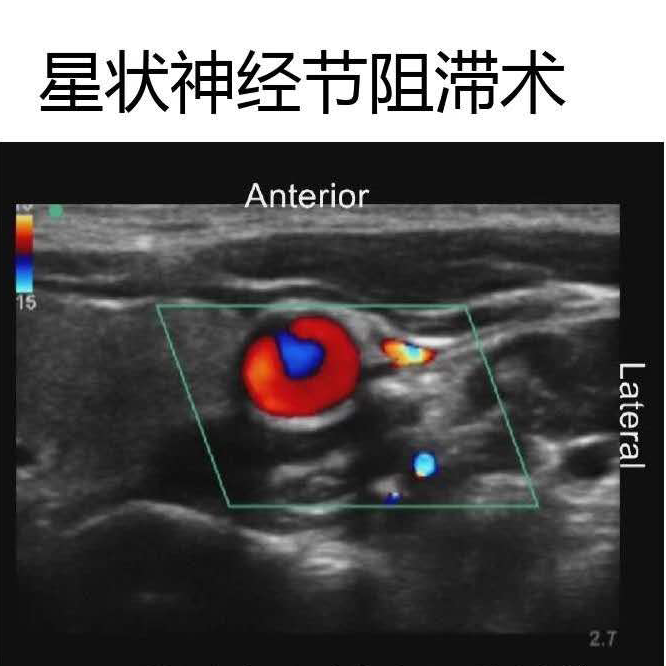

如星狀神經(jīng)節(jié)阻滯術(shù)

超聲多普勒技術(shù)可以清楚的觀察到血管

提高對于局部解剖的觀察

(神經(jīng)及周圍結(jié)構(gòu)的回聲表現(xiàn))